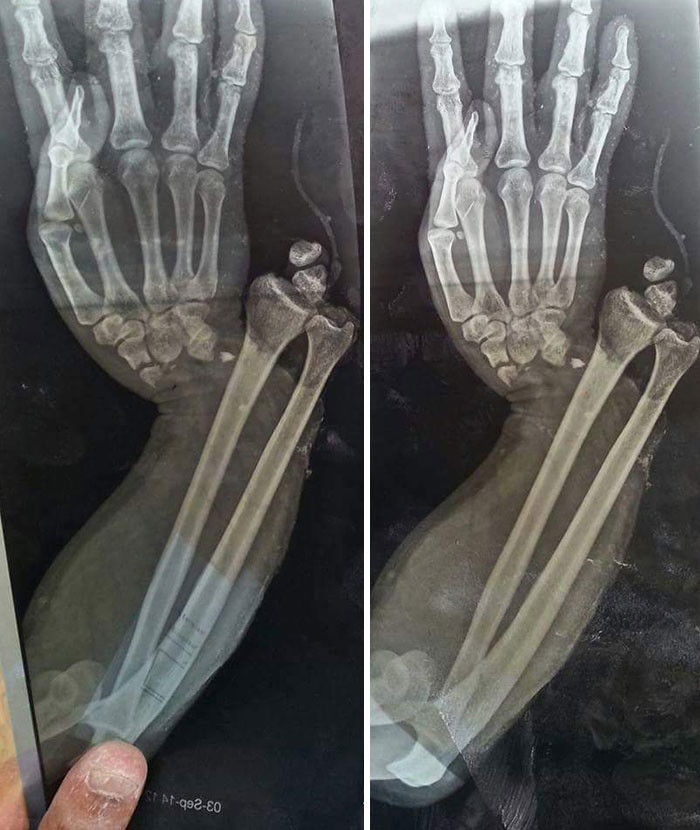

文章插图

看着都痛